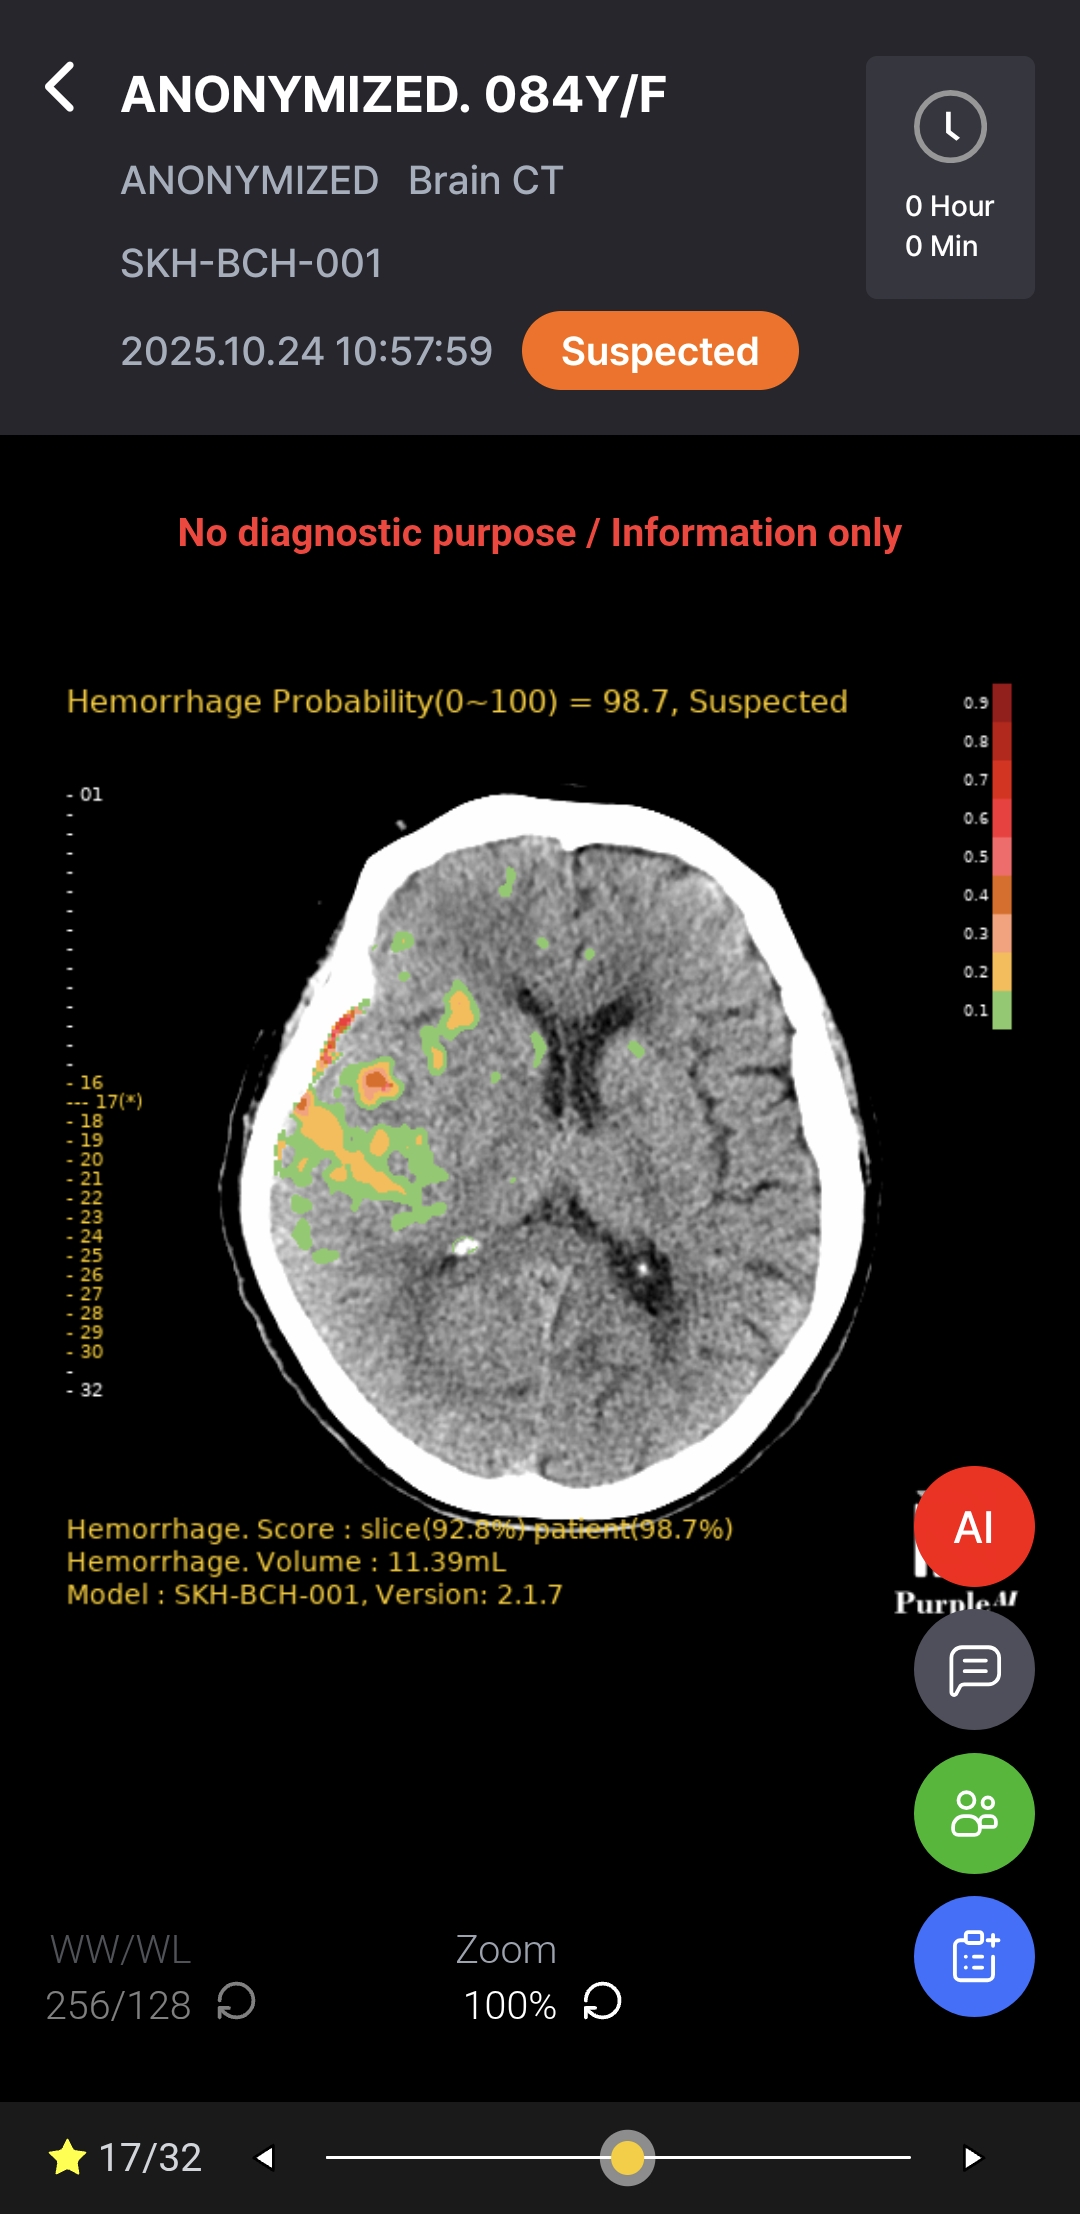

AI-powered diagnostic support for rapid, accurate detection and localization of brain hemorrhages on non-contrast CT, with ROI visualization and volume quantification to help radiologists assess hemorrhagic regions.

As a Radiological Computer Aided Triage And Notification Software, Hyper Insight™ – ICH functions as a triage and notification tool – supporting, not replacing, medical judgment. Final diagnosis and treatment decisions remain the responsibility of qualified medical professionals.